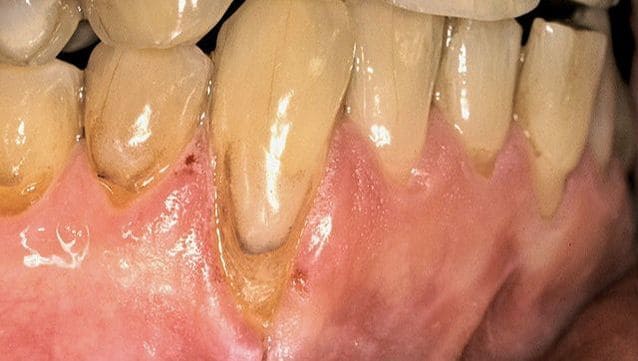

Before